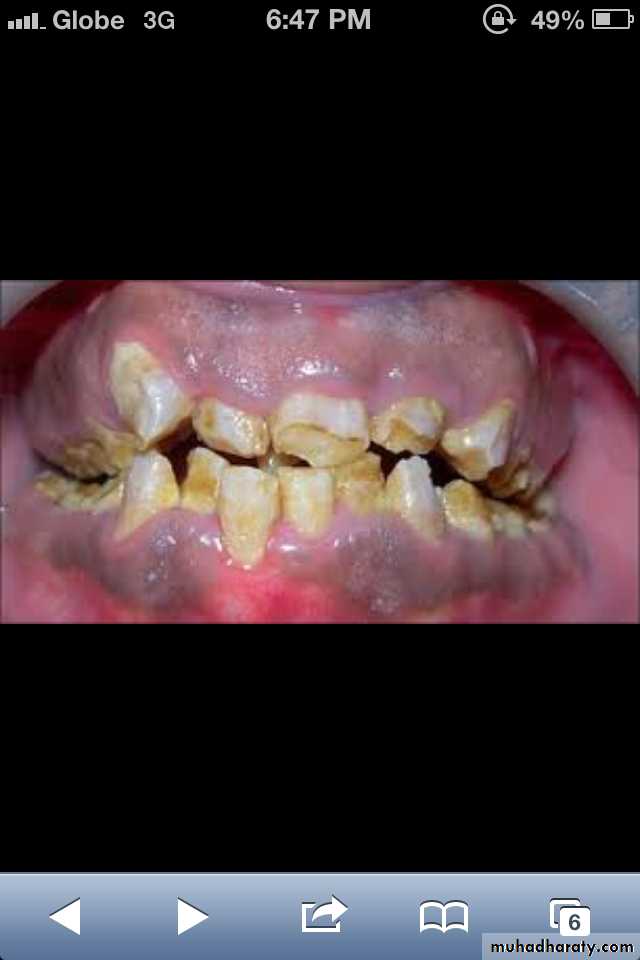

Amelogenesis Imperfecta

*It is a developmental disturbance that interferes with normal enamel formation.*It leads to marked changes in the enamel of all or nearly all the teeth in both dentitions.

*Most forms are autosomal dominant or recessive.

*Affects both dentition.

Enamel is composed mostly of mineral that is formed and regulated by the proteins in it. Amelogenesis Imperfecta is due to the malfunction of the proteins in the enamel.

* Classified based on pattern of inheritance:

hypoplasia.

hypomaturation.

hypocalcified.

* No treatment except for improvement of cosmetic

appearance.

Hypoplastic Amelogenesis Imperfecta:

* Due to some defect in ameloblasts enamel fails to develop to its normal thickness dentin exposed the tooth shows yellowish-brown color.*Enamel is randomly:

pitted .

rough OR smooth &glossy.

*The occlusal surfaces of the posterior teeth are relatively

flat with low cusps due to attrition of cusp tips that were initially low and not fully formed. An anterior open bite may be noted..

Generalized hypoplastic type

Amelogenesis ImperfectaAffects primary &permenant dentition

Severe mottling of the enamel surface.

Hypocalcified Amelogenesis Imperfecta:

*Enamel matrix is formed in normal quantity,poorly calcified.

When newly erupted:Enamel is normal in thickness, normal form, but weak , and opaque or chalky in appearance.

With years of function:

Coronal enamel is removed except for cervical portion that is occasionally calcified better.